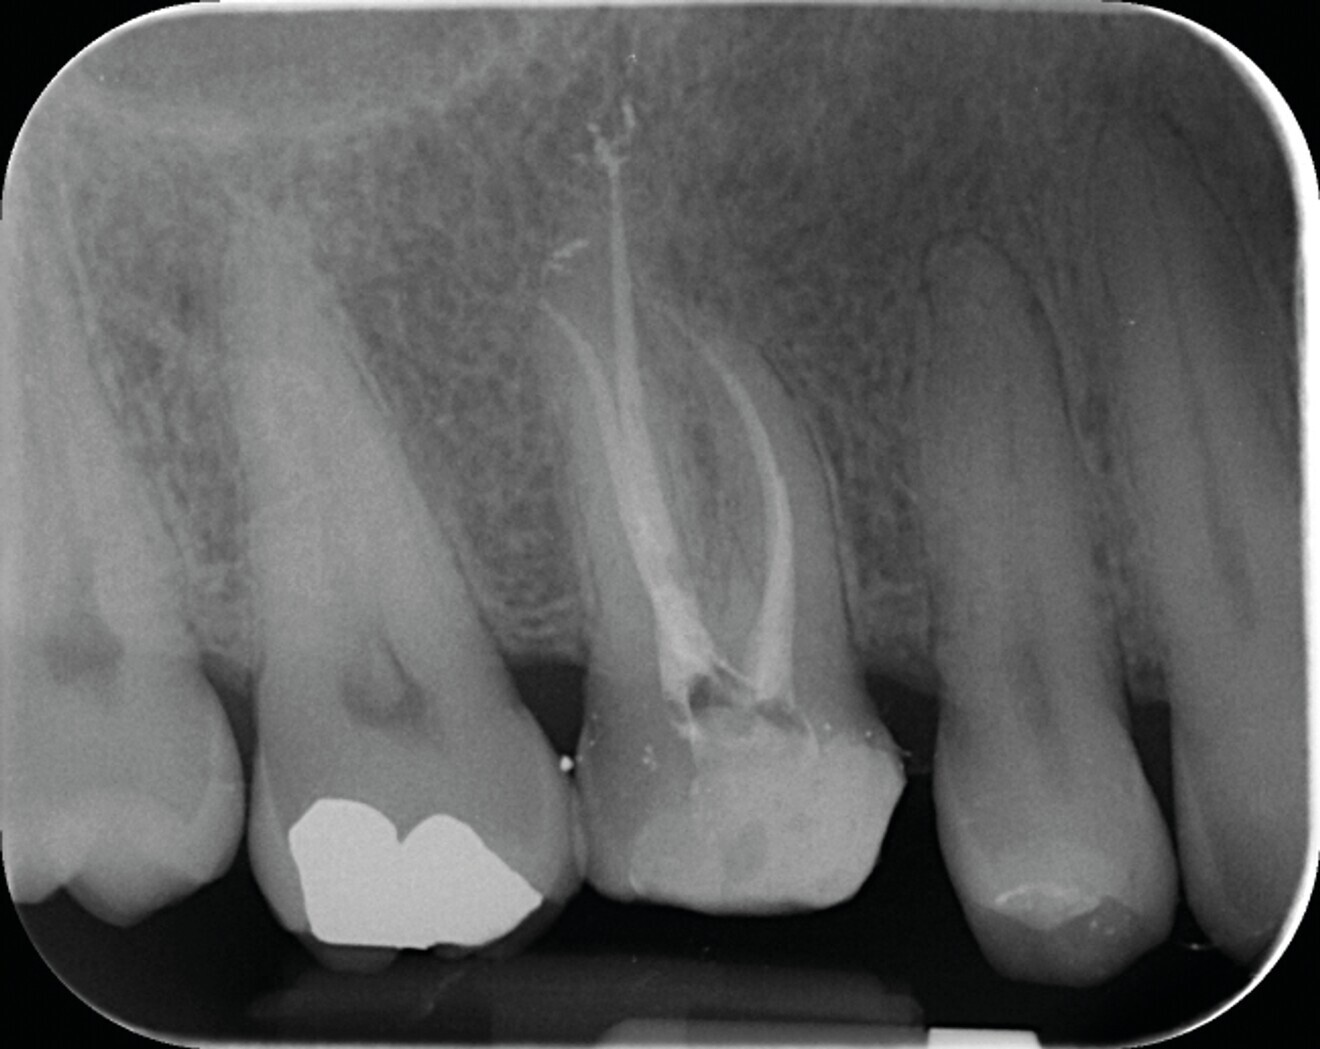

Fig. 7a : Traitement canalaire d’une molaire mandibulaire réalisé avec le système SlimShaper (Zarc – Endoboutik) et obturation avec le CeraSeal (Komet). (a) Radiographie préopératoire.

Fig. 7b : Radiographie postopératoire mettant en évidence la préservation maximale de tissu dentaire dans la partie cervicale de la dent, grâce au système SlimShaper. Cette mise en forme préservatrice n’a pas interféré sur le reste de la procédure, elle permet surtout d’éviter d’affaiblir la dent dans la zone cervicale.